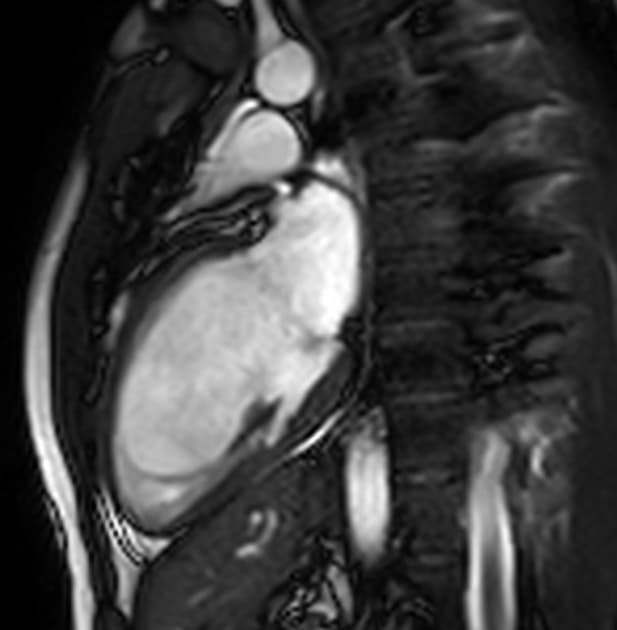

2ch Cine SSFP

Chất lượng hình ảnh: có artefact hô hấp từ nhẹ đến trung bình, các yếu tố khác không gây hạn chế

Phân tích hình thái và chức năng (tính toán thể tích nội tâm thất – bao gồm cả cơ cột tì):

- Vùng co bóp giảm nhẹ, đặc biệt ở các đoạn đáy vách liên thất dưới và thành dưới.

- Kích thước tâm nhĩ nhìn thấy bình thường.

- Không thấy tổn thương van tim đáng kể.

- Không thấy huyết khối trong buồng tim.

- Không thấy tràn dịch màng ngoài tim (pericardial effusion).

Hình ảnh cộng hưởng từ tim (Cardiac MRI) phù hợp với viêm cơ tim mạn tính (chronic myocarditis).

Hình ảnh cộng hưởng từ cho thấy viêm cơ tim mức độ nhẹ, kèm phù cơ tim nhẹ và các dấu hiệu tổn thương cơ tim không do thiếu máu cục bộ (non-ischemic myocardial injury) ở một bệnh nhân có phân suất tống máu giảm nhẹ được phát hiện trong khám sức khỏe định kỳ hàng năm dành cho phi công. Trong thời gian nằm viện ngắn, chẩn đoán suy tim với phân suất tống máu giảm nhẹ (heart failure with mildly reduced ejection fraction – HFmrEF) đã được xác lập. Các nguyên nhân như bệnh động mạch vành, bệnh van tim và rối loạn nhịp tim đều đã được loại trừ1, và một cuộc cộng hưởng từ tim ngoại trú với đặc trưng hóa mô cơ tim đã được thực hiện như một phần trong quy trình chẩn đoán thông thường2. Việc phù cơ tim chỉ tăng rất nhẹ cho thấy tình trạng viêm đã ở giai đoạn mạn tính. Khai thác kỹ tiền sử bệnh lý của bệnh nhân cho thấy bệnh nhân từng mắc COVID-19 nặng cách đây khoảng 1 năm, điều này củng cố thêm chẩn đoán.